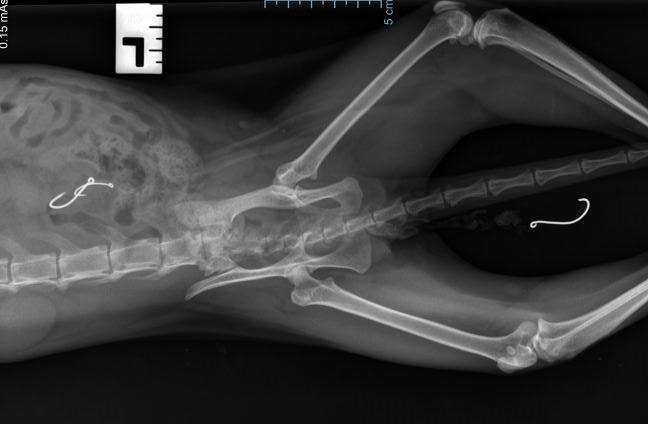

Horrified at realising that poor Sherbet had at some point ingested fishing lines, she was rushed back to the vet. After an X-ray, our team were shocked to see that there were two more fish hooks inside her bowels, with the third still hanging outside of her body with the lines.

Two more fishing hooks were found inside Sherbet's bowels.